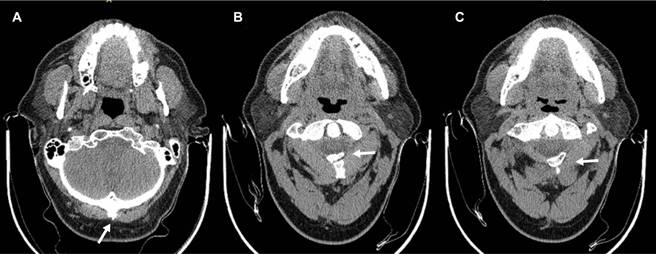

Con manifestaciones clínicas relacionadas con circulación de arterias vertebrales, se solicitaron radiografías AP, lateral y proyección transoral (Figura 1), las cuales revelaron: escoliosis cervical izquierda, inversión de la lordosis con vértice en C4-C5, anterolistesis de C4/C5 grado I, disminución de los espacios discales C3-C4 y C6-C7 por discartrosis, así como ausencia de arco posterior del atlas, con presencia sólo de tubérculo posterior, además se observa osteofito en protuberancia occipital externa. Se solicitaron radiografías dinámicas y tomografía computarizada de columna cervical, las primeras mostraron verticalización del tubérculo posterior del atlas a la flexión, y horizontalización del mismo en extensión, además de anterolistesis C4/C5 (Figura 2), la tomografía confirmó diagnóstico de anomalía congénita del atlas tipo D de la clasificación de Currarino (Figuras 3 y 4). Se prescribió collarín blando para limitar parcialmente la movilidad de columna cervical, se indicó evitar flexo-extensión máxima de columna cervical durante actividades laborales, así como evitar lectura o ver televisión en cama. Se canalizó a valoración por neurocirugía de la anterolistesis C4/C5, responsable a nuestro juicio de la sintomatología del paciente, neurocirugía le propuso fijación C4-C5, a lo que el paciente se negó, fue remitido nuevamente a rehabilitación para tratamiento por considerar que la anomalía congénita no era responsable de sintomatología, se aplicaron 10 sesiones de fisioterapia a columna cervical a base de compresas químicas y ultrasonido a dosis de 1.5 watts/cm2, así como ejercicios de fortalecimiento muscular de paravertebrales aunado a las indicaciones antes anotadas, se dio de alta de rehabilitación asintomático, con cita abierta a neurocirugía en caso de reanudar sintomatología.

Figura 2: Proyecciones dinámicas de columna cervical que muestran: verticalización del tubérculo posterior del atlas durante la flexión, y horizontalización del mismo a la extensión, además de la anterolistesis C4/C5.